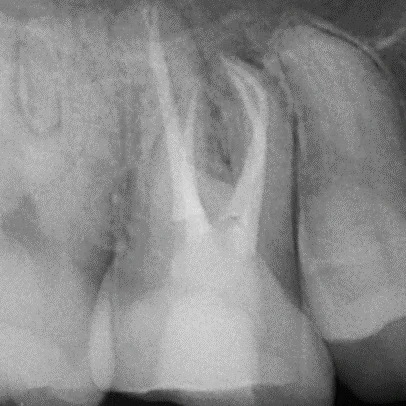

- 過去的根管治療失敗,需要重新根管治療

- 診斷與評估:牙醫透過X光片和臨床檢查確認受影響的牙髓狀態。

進階的根管治療技術,如顯微鏡根管治療,提供了更大的視野和精確照明,使得治療更為精確和效率更高。

這種方法不僅增加了治療的成功率,也減少了患者的不適感。此外,先進的超音波設備和專用根管銼針等工具,能更有效地清理根管內的感染物質。